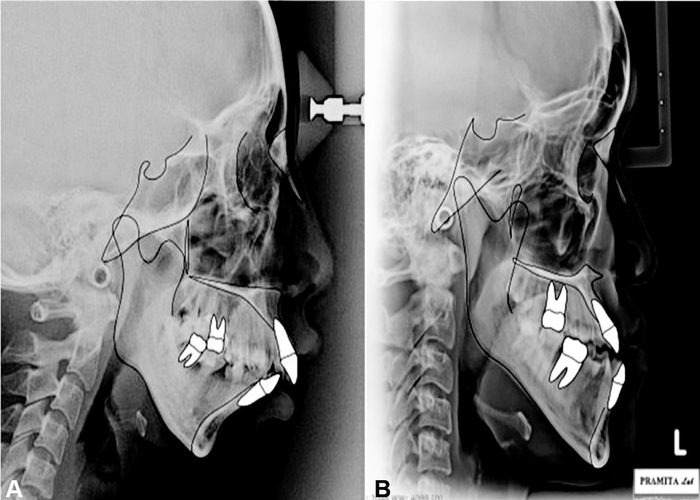

Mandibular Plane Angle

View attachment 4054612 View attachment 4054616

Animation Range: 0º to 45º Below Horizon

Ideal Pitch: 12.5º Degrees Below Horizon

Orbitomaxillary Plane Angle

View attachment 4054618 View attachment 4054620

Animation Range: 2.5º Inward to 30º Outward

Ideal Yaw: 25º Outward

Temporal Plane Angle

View attachment 4054621 View attachment 4054622

Animation Range: 0º to 30º

Ideal Yaw: 10º